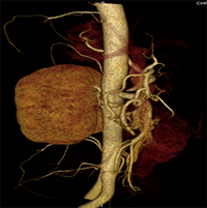

同一病人利用容積數(shù)據(jù)進行三維處理后,高品質MPR和三維圖像上則清晰顯示了縱向排列的腹腔干與腸系膜上動脈相鄰近,血管發(fā)生變 異,近端血管閉塞,為臨床提供了精確的診斷信息。

從上面的例子可以看到,能否為臨床提供高品質的三維影像成為了16層CT的核心價值,而東芝新一代的 全景三維16層CT擁有最為  先進的3項核心技術,在16層核心價值上的表現(xiàn)自然值得期待。

TCOT+----------全景三維重建算法

三維影像最核心的價值在于高精度的重現(xiàn)人體真實的三維結構,而以往的CT在采集中受到錐形線束偽影的影像視野邊緣的數(shù)據(jù)不足,因而傳統(tǒng)的重建算法獲得三維圖像易出現(xiàn)邊緣失真,進而影響臨床診斷。

東芝專利的TCOT+算法基于AQUILION ONE動態(tài)容積CT的全景重建技術,最大限度的抑制了錐形線束偽影對三維圖像的影響,使邊緣數(shù)據(jù)量增大了25%,從而實現(xiàn)。